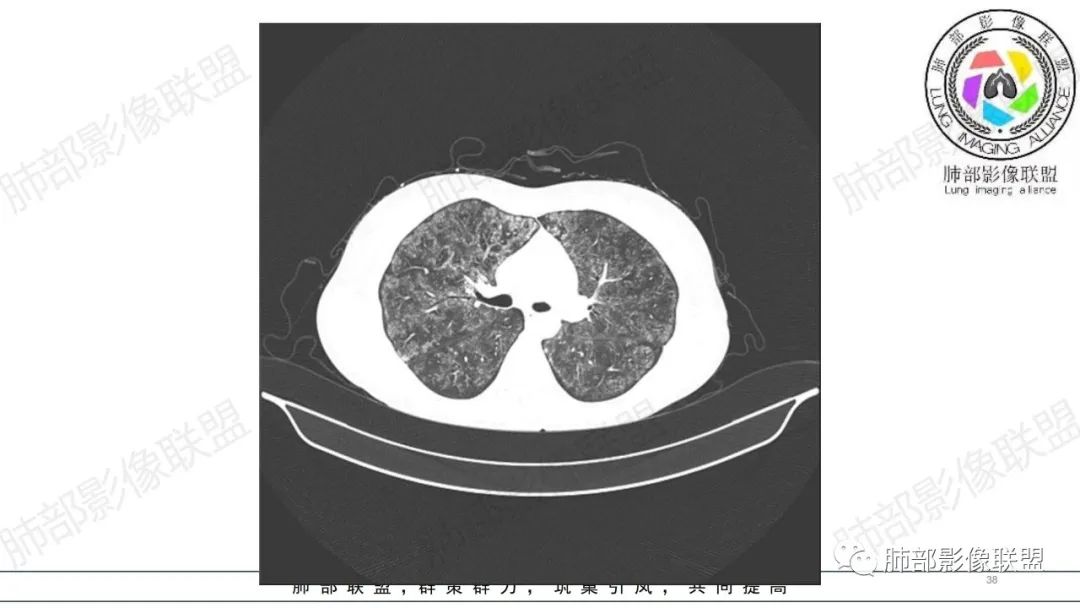

34岁女性患者,“哮喘”病史30年,近期有可疑刺激性气体吸入史;因乏力半年,咳嗽、憋气、发热4天就诊;6.1CT提示双肺广泛毛玻璃影及粟粒样结节,胸膜下闲置及血管周闲置,可见树丫征,部分小叶间隔增厚。考虑:1.过敏性肺泡炎,有可疑刺激气体接触史,胸膜下闲置,广泛毛玻璃影,地图样分布,粟粒结节边界模糊,支持过敏性肺泡炎,但糖皮激素治疗效果不佳,且动态复查血常规血红蛋白进行性降低,过敏性肺泡炎 不符合;2.肺含铁血黄素沉积症:患者30“哮喘”病史,可能为肺含铁症状,肺部CT提示双肺弥漫毛玻璃影及粟粒结节影,中下肺明显,肺底部分小叶间隔增厚,近期咳嗽、憋气、发热,血常规血红蛋白进行性下降,考虑肺含铁急性期症状,但临床无咯血症状,肺含铁不典型。综合考虑:肺含铁血黄素沉积症>过敏性肺泡炎。

年轻女性 ,急性喘息发热,肺部影像弥漫磨玻璃密度,部分细小腺泡结节,胸膜下黑线显示,短期复查,病变密度增高,下肺明显,血管周围肺组织累及较少、且逐渐成小叶间隔分布。考虑弥漫肺泡内病变,并经淋巴道转移,下肺比上肺明显,多为免疫细胞功能下肺较强。1.过敏性肺泡炎,有相关病史,三层密度特点、头尾测分布,符合。2 肺泡微石症,多有钙化,且缓慢起病,病程不太符合,放待排。3 吸入相关肺损伤,有病史,疾病演变过程也符合渗出-肉芽肿改变,建议详细询问病史。4 感染性病变,结核?病变气道分布为主,如此弥漫且没有树丫不符合。5.巨细胞病毒,可以磨玻璃 结节 改变,没有免疫缺陷病史。最后考虑吸入所致 1过敏性肺泡炎、吸入性肺损伤 鉴别肺泡微石症。

肺内气腔磨玻璃结节,肝脾肿大,治疗后间质改变,弥漫大B可能